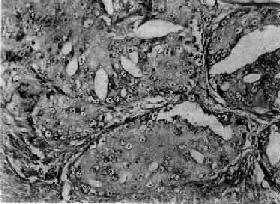

镜下,97%的前列腺癌均为腺癌,少数为移行细胞癌和鳞状细胞癌。依其分化程度可分为高分化、中分化和低分化3型。高分化前列腺癌最多见,癌细胞排列成大小不等的腺样结构,颇似前列腺增生腺体,但癌细胞体积较小,核较深染,上皮细胞往往呈多层排列并较不规则(图14-4),有时可呈乳头状腺癌或腺泡腺癌结构,并常可见癌组织向间质浸润生长;中分化腺癌全部或部分呈腺样结构,但腺体排列较紊乱,核异型性较明显,且有时形成筛状结构;低分化腺癌的癌细胞一般较小,排列成实体团块或条索,腺腔样结构很少(图14-5)。多数病例乃由上述多种组织结构混合组成。

图14-5 前列腺癌(低分化型)

癌细胞异型明显,并呈筛状结构